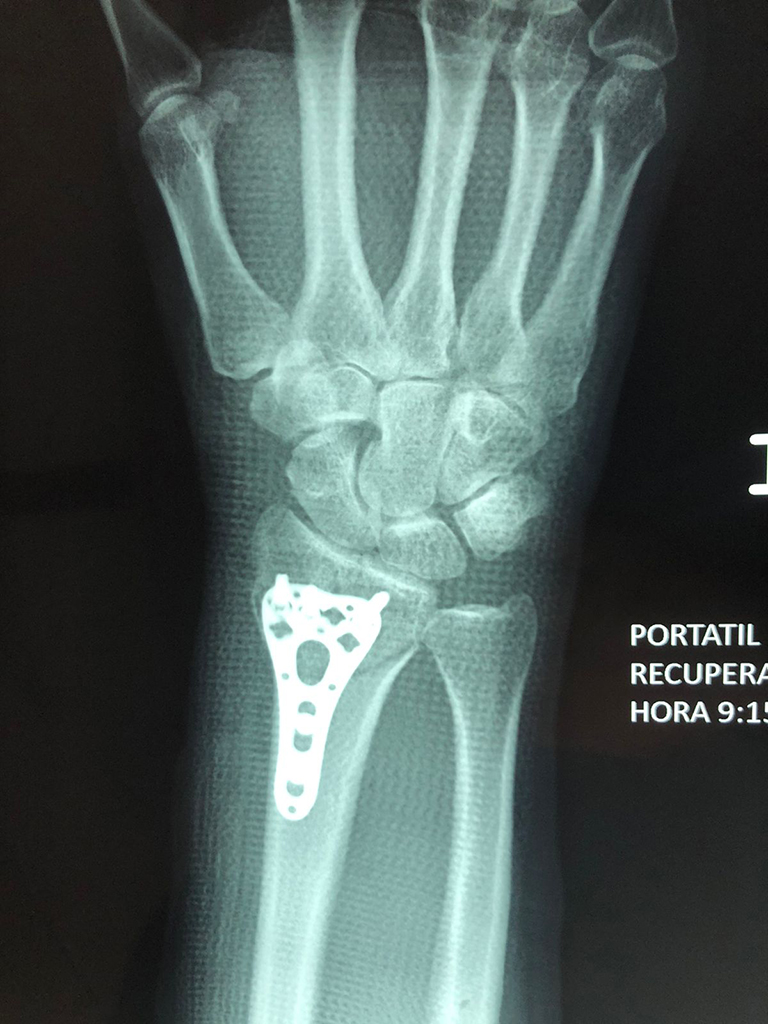

Cirugías de Codos - Cirugías de Muñecas y Manos

Los procedimientos más comunes en cirugía de la mano son aquellos destinados a reparar traumatismos, incluyendo lesiones de tendones, nervios, vasos sanguíneos, y articulaciones; huesos fracturados; y quemaduras, cortes, y otros daños de la piel.